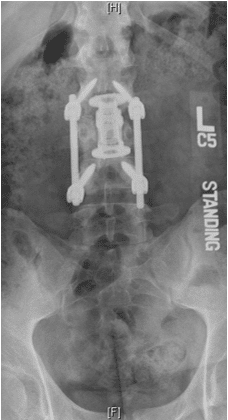

Patient was operated and the spinal canal cleaned up of all bony fragments. The spine was fixed from the side and the back to take care of instability.